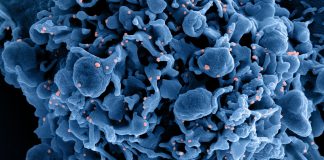

COVID-19 è una malattia infettiva respiratoria causata dal virus denominato SARS-CoV-2 appartenente alla famiglia dei coronavirus. Una malattia infettiva causata da un nuovo virus mai identificato prima negli esseri umani.